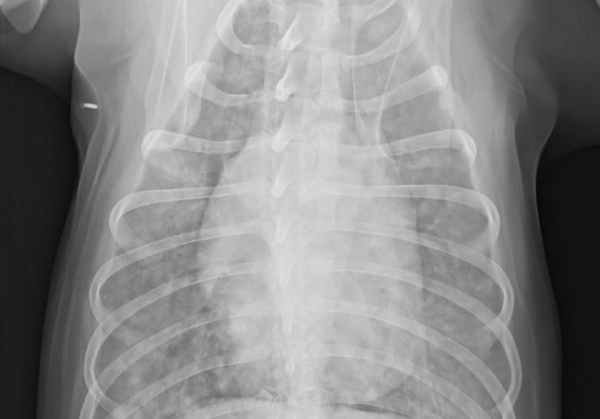

X光照片顯示肺部充滿白色小白點,顯示腫瘤擴散嚴重的程度....